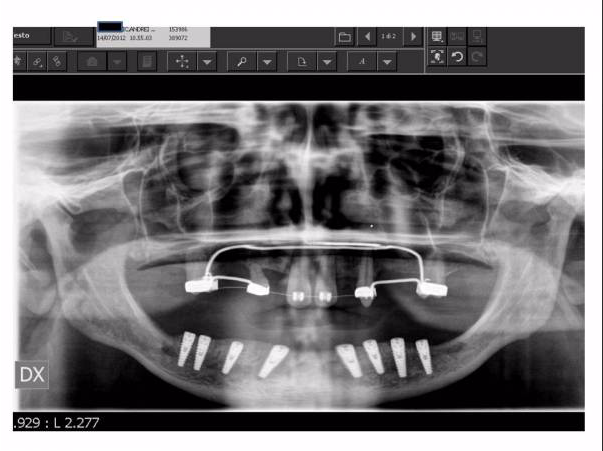

Lo schema con impianti inclinati nell'arcata mandibolare (inferiore) per evitare i forami mentali e ottenere in ogni caso un considerevole stabilità primaria per il carico immediato.

Le soluzioni più moderne rispetto al Toronto Bridge originale prevedono un trattamento abbastanza simile tra le due arcate. Gli impianti, se necessario, si inseriscono non paralleli tra loro ma con una inclinazione di circa 30° allo scopo di evitare i forami mentali nell'arcata inferiore e i seni mascellari nell'arcata superiore: l'obiettivo è ottenere una buona stabilità primaria degli impianti (necessaria anche per il carico immediato) anche in assenza di struttura idonea nelle zone posteriori evitando trattamenti più complessi con innesti di osso. Il posizionamento disparallelo/inclinato prevede necessariamente una componentistica del sistema implantare che permetta successivamente la protesizzazione degli impianti disparalleli. Infatti per gli impianti inclinati è prevista un protesizzazione con doppio moncone, un primo inclinato rispetto all'asse lungo dell'impianto (generalmente di 17°, 30° o addirittura 40-45°) ed un secondo in asse con l'emergenza del primo.